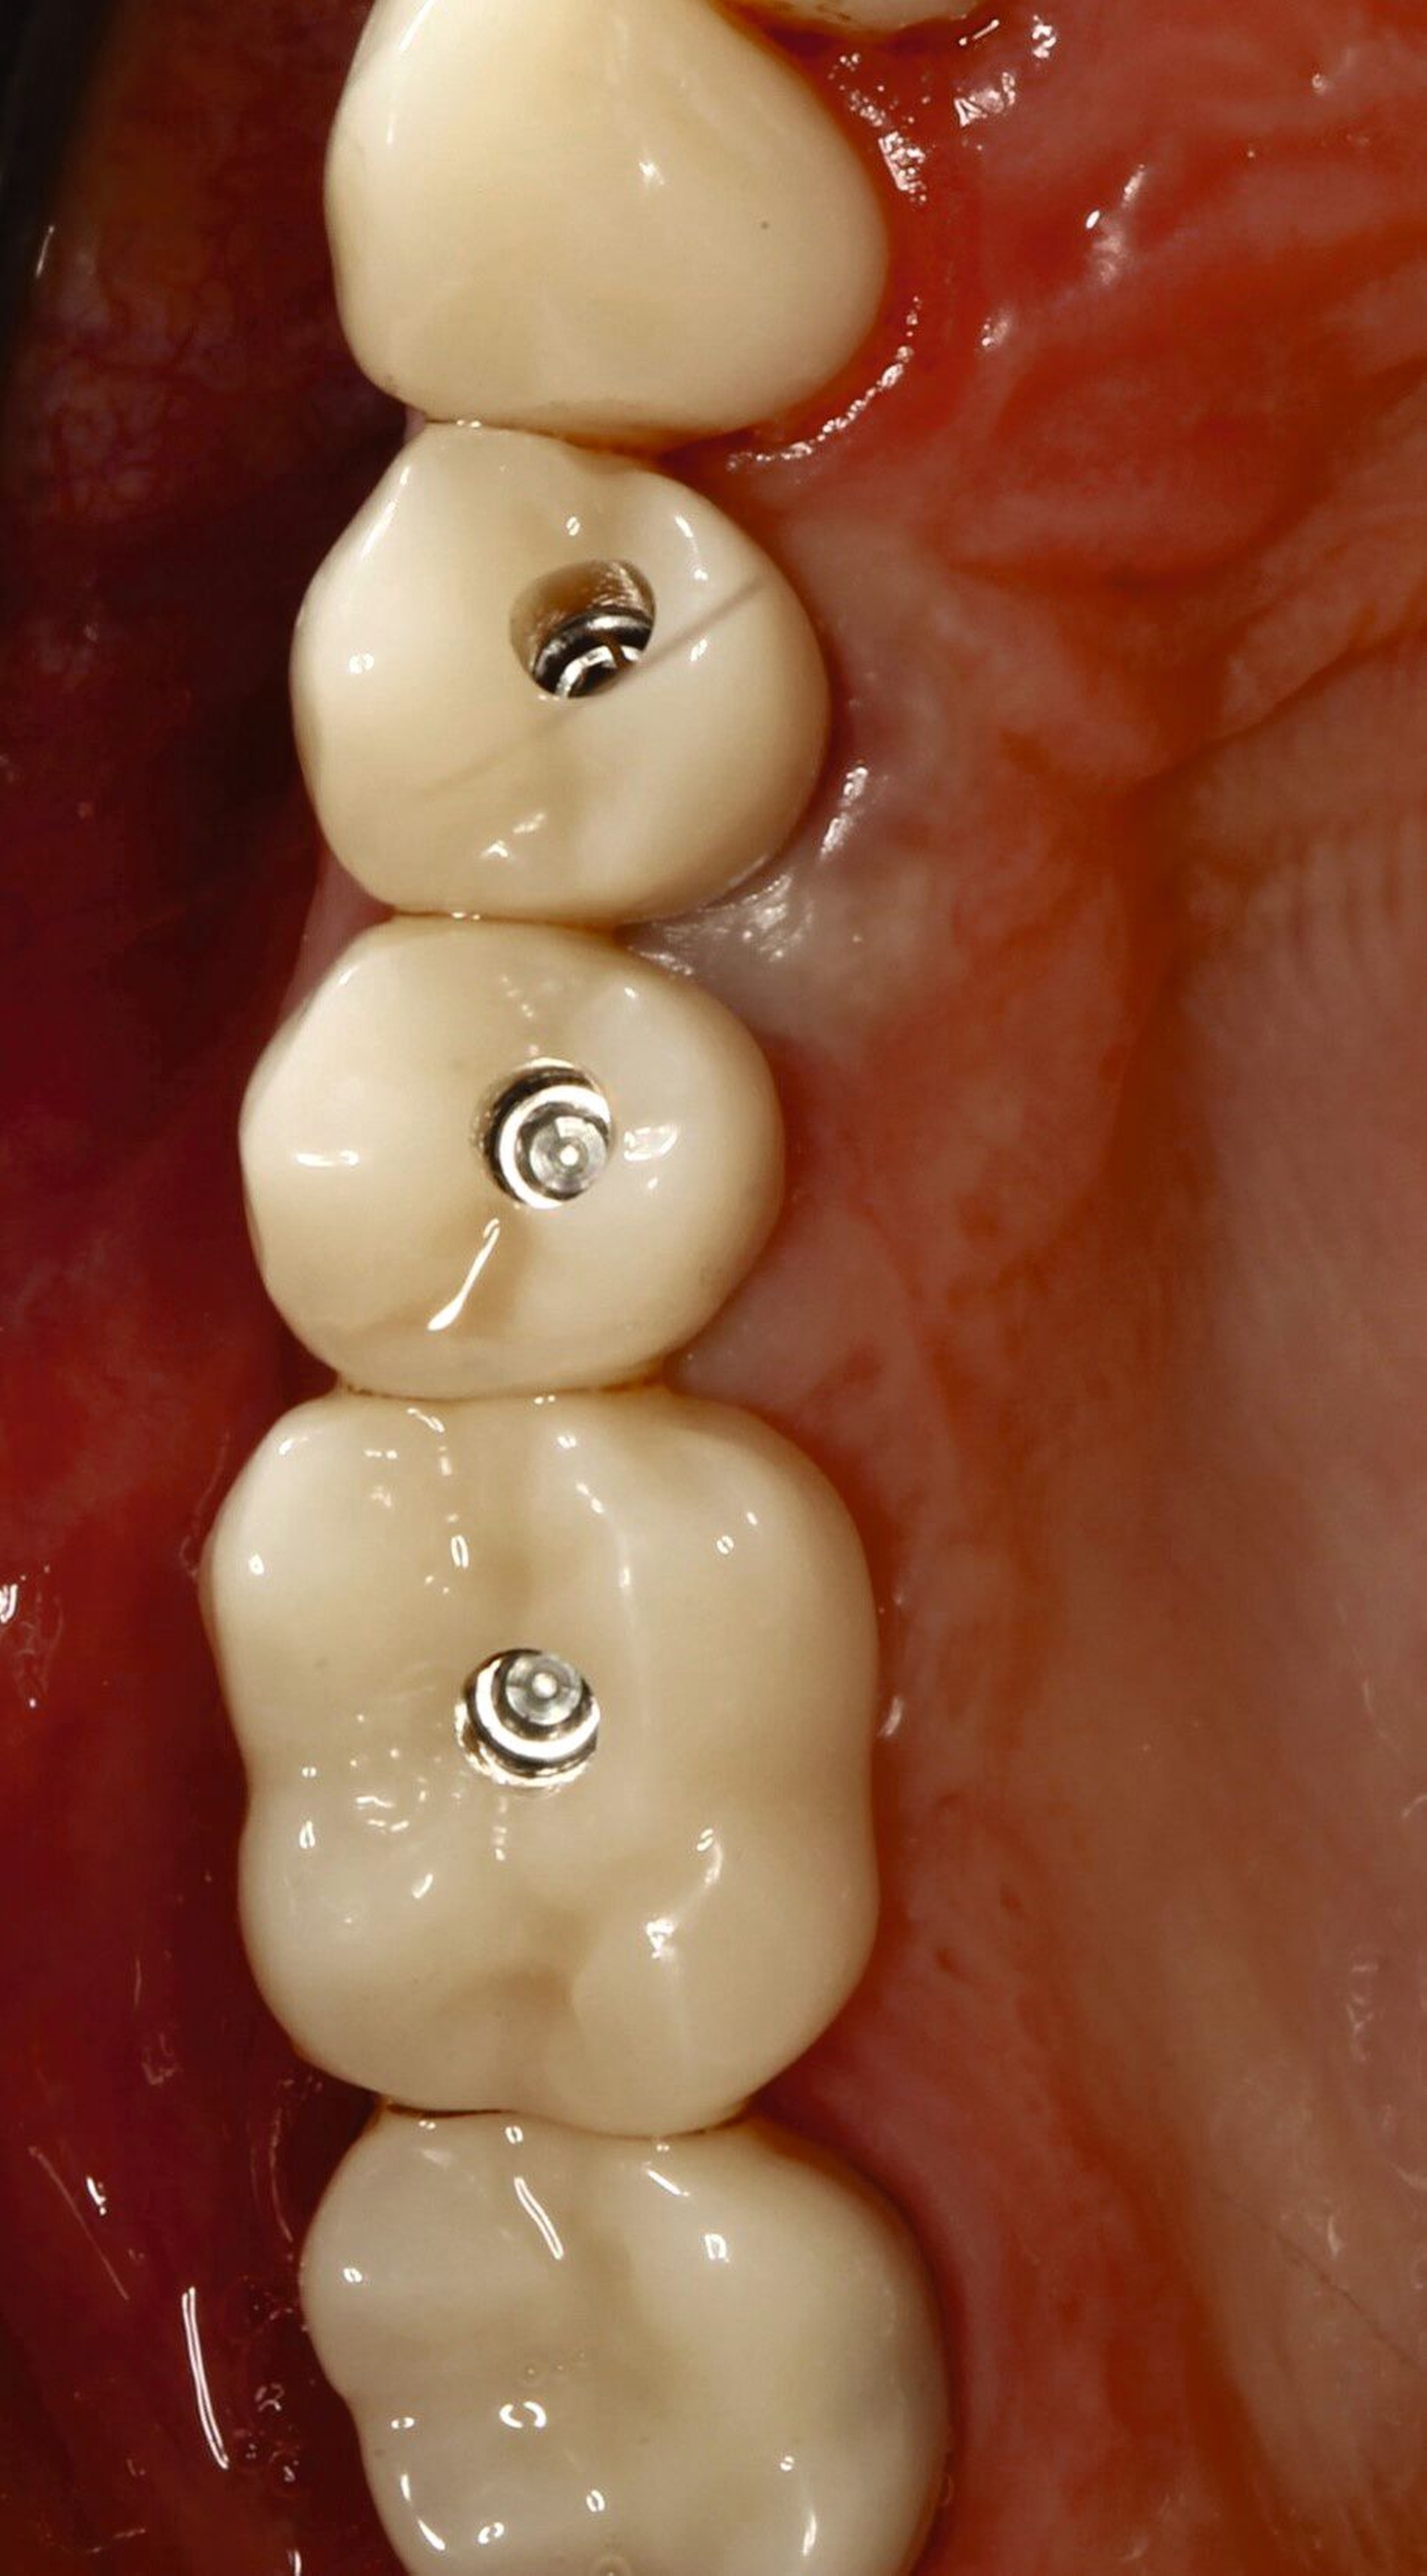

Eine zusätzliche Maßnahme, um das Weichgewebe zu optimieren, ist nicht notwendig und das angestrebte Okklusionskonzept kann umgesetzt werden, wobei die implantatprothetische Restauration nur minimal im Kontakt steht. Dies ist in vielen Fällen nur schwer umzusetzen. Wird die Restauration voll in statischer Okklusion belastet, bekommt die Restauration das Label A. Im vorliegenden Fall wird die Implantatkrone in gewisser Weise von den Nachbarzähnen geschützt, befindet sich aber dennoch in Okklusion (Abbildung 5). Für Implantatkronen, wie in diesem Fall, wird das Okklusionsschema so angepasst, dass die Shimstock-Folie im Schleifkontakt durchgehen kann. Situationen ohne okklusale Parafunktionen stellen ein geringes Risiko dar. Dann entscheidet der Zeitpunkt der Belastung über das Risiko, wobei spät und früh belastete Implantate dasselbe geringe Risiko haben. In unserem Fall zeigt der Patient Anzeichen einer Parafunktion, sodass den Unterkieferbewegungen und der okklusalen Morphologie der Restauration besondere Aufmerksamkeit gewidmet werden muss.

In der vorgestellten Situation wird kein therapeutischer Zahnersatz (Langzeitprovisorium) benötigt, daher bekommt unser Fall das Label S. Kann eine verschraubbare Krone verwendet werden, erhält diese ebenfalls das Prädikat S, die zementierte Restauration wird mit einem höheren Risiko bewertet.

Fall 2 – complex (chirurgisch/prothetisch)

Der zweite Fall zeigt, dass nicht alle implantologischen Behandlungen chirurgisch als straightforward (S) eingestuft werden können. Während im Straightforward-Fall ein Behandler ausreichte, war im komplexen Fall die Expertise von zwei spezialisierten Kollegen nötig. Dies verdeutlicht, dass die Einschätzung der Komplexität vor Behandlungsbeginn entscheidend ist, um den optimalen Behandlungsweg zu wählen und das bestmögliche Ergebnis zu erzielen.